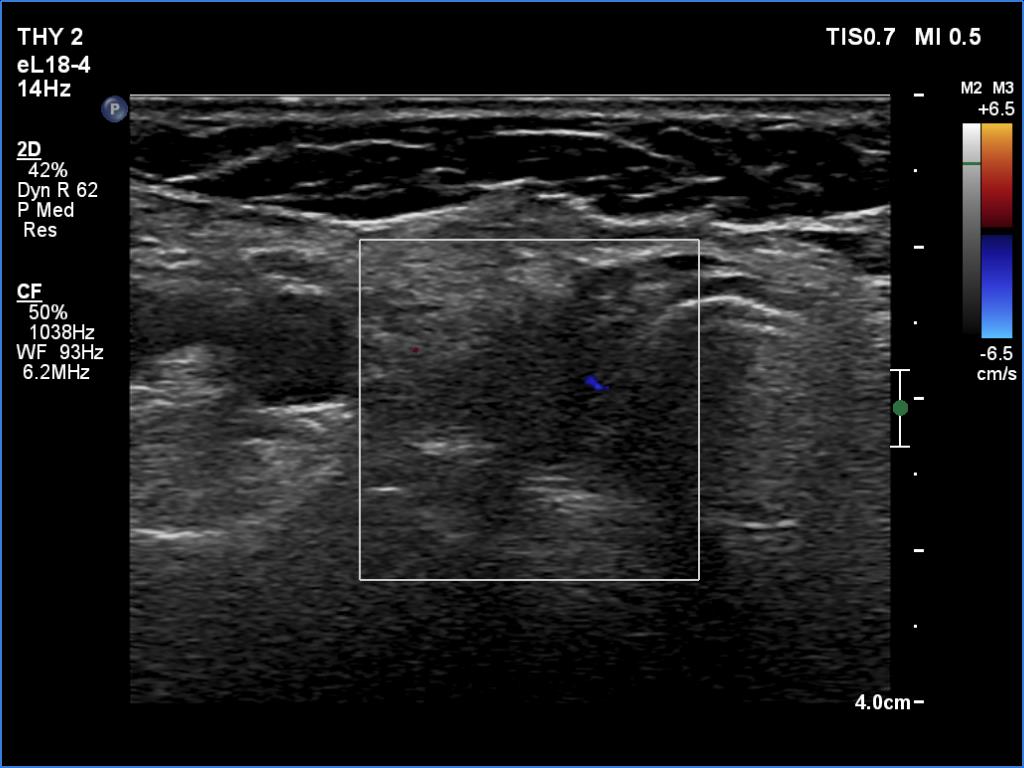

Second examination 6 years later (third row of images):

Clinical data: The patient came to a routine follow-up. She had no complaints which could be related to thyroid disease.

Palpation: no abnormality.

Result of blood test: TSH 7.03 mIU/L on daily 75 microgram levothyroxine.

Ultrasonography. The remnants of the thyroid lobes have significantly decreased. Otherwise, the pattern remained the same: a central larger hypoechoic field was surrounded with echonormal tissue.

Suggestion: to increase the dose of the levothyroxine to daily 100 microgram.

Comment. It is worth analyzing the ultrasound presentation - a large hypoechogenic area is surrounded with a thick echonormal rim. Although this pattern seems to be a nodule, it is one of the most characteristic appearances of a subtotally resected thyroid.